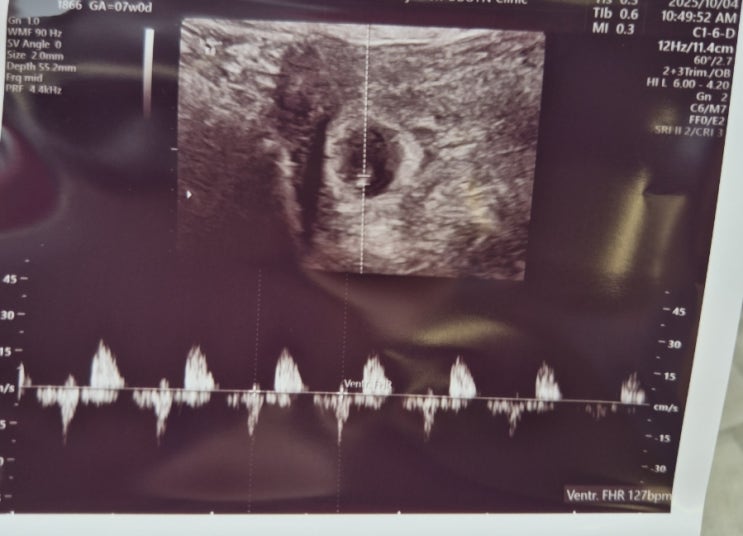

임신일기 / 6주~7주 난황과 심장소리

임신일기 / 6~7주 난황과 심장소리 휘몰아쓰는 임신일기.. 임신 후.. 무기력해짐과,, 입덧의 시작으로 몸의...